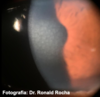

O que é anel de Fleischer?

Anel de ferro presente na base do ceratocone

Fonte: columbia eye